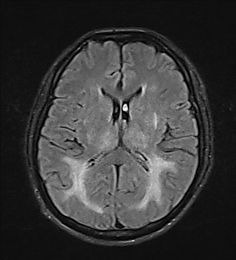

Refer to caption

Figure 1: MRI Scans Showing Various Conditions: Glioma, Meningioma,a Non-Tumor Case and Pituitary Tumor

A few images from each class were visually inspected to understand dataset balance and quality, with examples shown in Figure 1. The varying nature of gliomas, meningiomas, pituitary tumors, and non-tumor cases hence brought a firm rationale before the model building and evaluating stages.